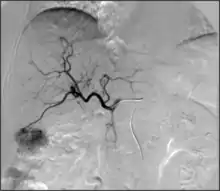

- Embolization: The goal of embolization is to decrease or stop flow only in a target vessel, while avoiding cutting off the flow to nearby non-target vessels. This can be performed to stop active bleeding (as in trauma[82]) to limit anticipated blood loss (such as in a complex surgery), or to cut off blood supply to either an abnormal vessel (e.g. aneurysm[83]) or abnormal structure (e.g. tumor). There are many embolic agents available, from metallic plugs and coils to various biologically compatible particles and glues.[84] Depending on the clinical situation, embolization can be temporary or permanent.

Acute or active bleeding can occur throughout the human body due to a variety of causes. Interventional radiologists can address bleeding with embolization, usually with small plastic particles, glues or coils. Traumatic rupture of a blood vessel, for example, may be addressed this way if a patient is at risk of fatal bleeding. This has revolutionized medicine and interventional radiologists commonly treat refractory nose bleeds, excessive coughing of blood, intestinal bleeding, post-pregnancy bleeding, spontaneous intra-abdominal on intra-thoracic bleeding, bleeding related to trauma and post-surgical bleeding. In some instances where severe bleeding is anticipated, such as in complex surgery or the excision of a highly vascular tumor, interventional radiologists may embolize certain target blood vessels prior to the operation to prevent major blood loss.